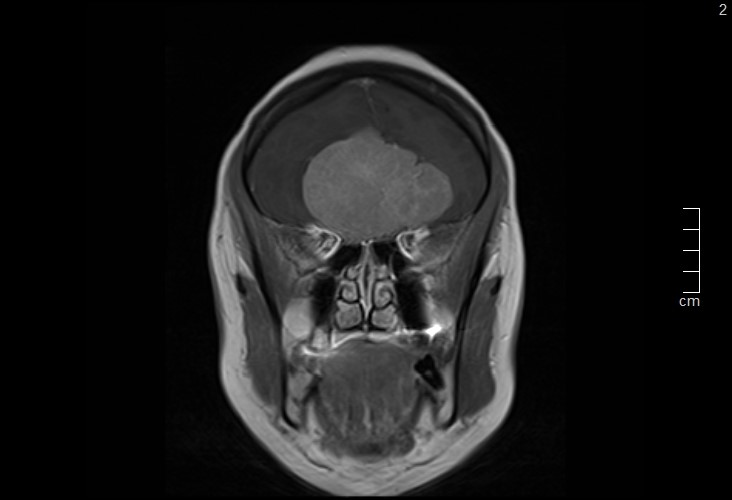

Figure 2. Coronal T1-weighted contrast-enhanced MRI demonstrating a bilateral, dural-based tumor arising from the olfactory groove with midline extension and mass effect on the optic pathways